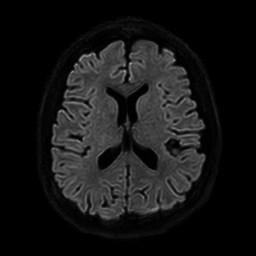

뇌 mri / 두정엽 부분 병변이나 위축되었는지요?

시공간 감각 저하(비현실감)와 바보가 되는 느낌(?)으로 최근에 mri를 촬영하였는데, 사진상 오른쪽에 구멍이 나있어서.. 질문드립니다.

저부분은 특별히 어디가 이상이 있거나 하는 것은 아닙니다.

그래서 환자분의 현재 증상에 대해서는 다른 접근을 해보셔야 하겠습니다.

정신과 진료도 한 번 고려를 해보시면 도움이 될 것 같습니다.